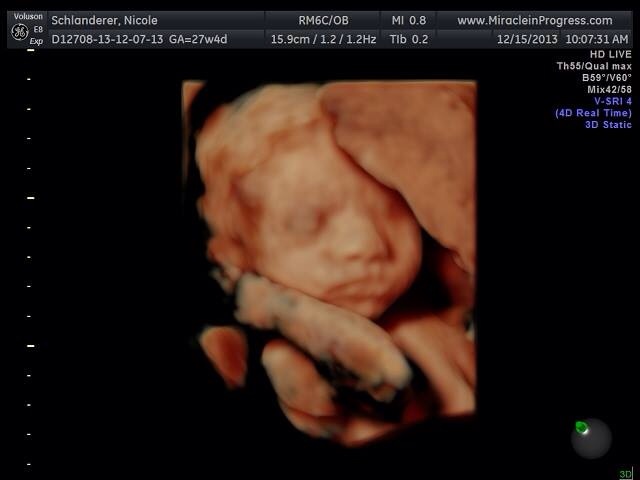

FYI - I tried to delete the first image because it has my full name, but it won't let me. Just don't hunt me down and murder me.

Me: 28 DH: 27